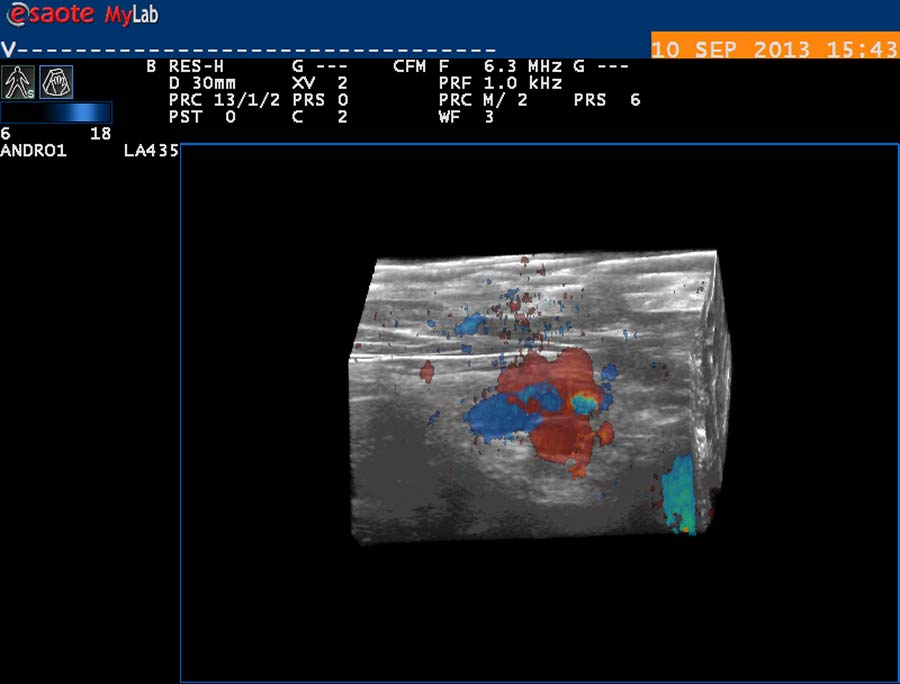

Před operačním řešením přinesou užitečné informace trojrozměrné (3D) záznamy o frekvenci 13 – 18 MHz, snímané v oblasti plánované operace. Mohou být ve formě bloku tkáně s Dopplerovským barevným mapováním cév, který je možné v 3D USG přístroji otáčet a prohlížet ze všech úhlů (obr. 36, 37), v podobě trojrovinného záznamu s pohyblivými kolmými rovinami (obr. 38,39) i v podobě kombinovaného záznamu (obr. 40). Mohou pomoci při plánování operačního přístupu.

obr. 36

obr. 37

Předoperační diagnostika - 3D Dopplerovská vysokofrekvenční ultrasonografie s 3D Color Flow Mapping Dopplerovským zobrazením spermatických cév poskytuje topografickou informaci o prostorovém rozložení struktur v oblasti, kterou budeme operovat (obr. 38 – 40). Podle nálezu plánujeme operaci. Operaci provádíme ze subinguinálního přístupu, kaudálně od anulus inguinalis externus. Neotevíráme přední stěnu inguinálního kanálu. Používáme stereoskopický 3D mikrochirurgický systém EyEMag a optoelektronický řetězec s operační kamerou s  variabilním zvětšením operačního pole – dříve na velkoplošné obrazovce (obr. 41,42), nyní s dataprojekcí na stěnu operačního sálu. Po uvolnění spermatického provazce tento anteponujeme před ránu a podkládáme měkkými plastovými hadičkami (obr. 43). Pečlivě revidujeme, zda nejsou přítomny extrafunikulárně probíhající venózní kolaterály; pokud je nalezneme, provádíme jejich ligaturu (obr. 44). Otevíráme zevní spermatickou fascii, za pomoci mikrovaskulární Dopplerovské sondy 16 MHz o šíři shodné s šíří arterie = 1 mm (obr. 45, 46) identifikujeme, preparujeme a prezervujeme spermatickou arterii. Ta má nejčastěji dvě hlavní větve - jednu povrchní, jednu hlubší (obr. 47). Izolaci od těsně naléhajících venózních větví je nutno věnovat dostatek času a opatrnosti, protržení stěny žilní vede k hemoragii a zhoršení přehledu v zorném poli. Manipulace s cévami při preparaci vede ke kontrakci jejich svaloviny, ke snížení perfuze a intenzity arteriálního Dopplerovského signálu. Aplikací muskulotropního spasmolytika (Buscopan) na stěnu cévní tuto kontrakci eliminujeme. Při ligaturách na arterii naléhajících vén kontrolujeme, zda dotažení ligatur nesnižuje průtok krve arterií (obr. 48). Ligatury provádíme materiálem firmy Ethicon – Johnson and Johnson o šíři 3/0 – 4/0. Dopplerovský záznam sledujeme ve formě akustické a grafické na obrazovce systému EzDop (obr.49). Vény, které nenaléhají na arterie, samostatně selektivně ligujeme (obr. 50, 51). Jako drenážní vény ponecháváme žíly provázející vas deferens, během operace hodnotíme stěnu těchto žil a jejich šíři. Dle předoperačního Dopplerovského vyšetření a peroperačního nálezu hodnotíme jejich funkční stav. Během preparace krevních cév prezervujeme pečlivě lymfatické cévy (obr. 52). Po kontrole kompletnosti výkonu a pečlivé hemostáze provádíme závěrečnou Dopplerovskou kontrolu zachování průtoku spermatickými arteriemi. Operujeme mikrochirurgickým instrumentáriem (obr. 53). Suturu zevní spermatické fascie provádíme atraumatickým Vicrylem 4/0, steh rány po vrstvách Vicrylem Plus 4/0, Vicrylem 3/0 a Vicrylem 3-4/0 Rapid (kůže). Incize kůže je délky asi 40 mm, podle vrstvy podkožního tuku (obr. 54). Výkon provádíme v cloně perorálním doxycyklinem 100 – 200 mg/ 1x 24 hodin, prevenci tromboembolické nemoci nízkomolekulárním heparinem.